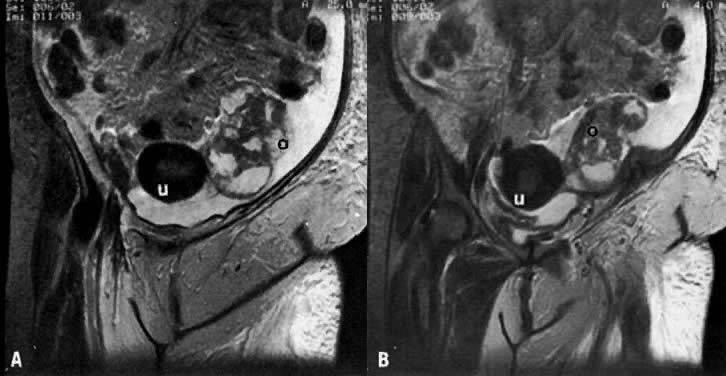

Fig. 32. A and B. Sequential coronal T2-weighted MRI of the pelvis in a patient with left ovarian carcinoma. Note that the left ovary ( o) is enlarged, lobulated, irregular, and inhomogeneous with areas of high and medium signal intensities. ( u, uterus.)